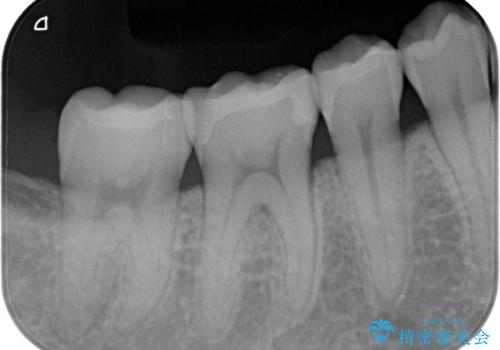

- 矯正終了後、昔詰めたプラスチックのやりかえを御希望されて3本セラミックにて治療を行いました。

プラスチックは経年的に劣化していて、虫歯の原因になることが多くあります。

今回の患者様も、プラスチックが劣化し着色が気になるとのことでしたがセラミックになってかなり喜んでいただけました。